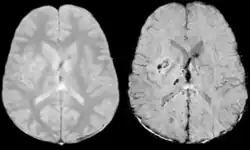

Die klinische Anwendung wird in verschiedenen Gebieten der Medizin erforscht:[4][5][6] Schädel-Hirn-Trauma,[7] Hirnschlag,[8] Cerebrale Amyloidangiopathie (CAA),[9] Gefäßmalformation (Sturge-Weber-Syndrom,[10] Cerebrale venöse Sinusthrombosen[11]), Multiple Sklerose,[12][13] Alzheimer-Krankheit[14] und Hirntumor.[15][16]